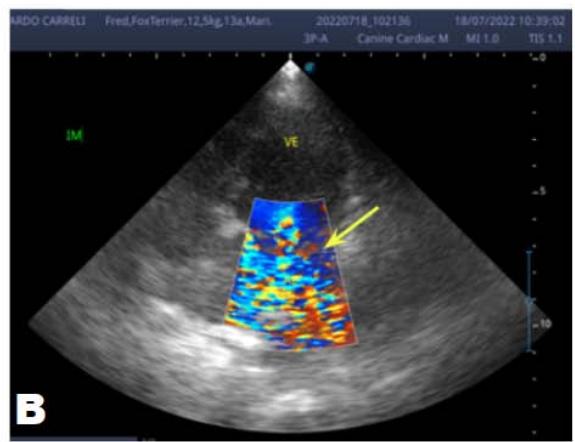

An echocardiogram (ECHO) (Figure 1) showed a thickened mitral valve and enlarged heart chambers. At first was prescribed Pimobendan PO at a dose of $0.25\mathrm{mg/kg}$ BID, continuous use, and requested to return in 30 days.

Figure 1: Echocardiogram 2021: Thickened/degenerated mitral valve (A); Observed in Doppler mode, significant mitral valve insufficiency (B); Hemodynamic assessment - Mitral regurgitation gradient: $3.45 \mathrm{~m} / \mathrm{s} / 47.68 \mathrm{mmHg}$; enlargement of left cardiac chambers; left ventricular diastolic dimension above normal limits was observed

In the reported, he was asymptomatic, and the echocardiographic examination showed enlargement of the left heart chambers, thickened and degenerated mitral valve (Figure 1), left ventricular diastolic dimension above normal limits. with normal systolic function parameters, characterizing systolic dysfunction. The thickening and degeneration of the mitral valve indicates its insufficiency, and the other changes represent diastolic dysfunction.